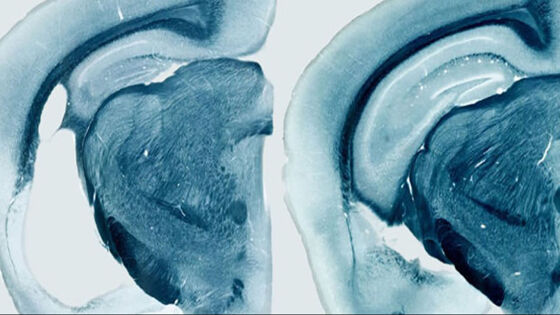

МОСКВА, 28 сен – РИА Новости. Биоматематики из Института системной биологии в Москве и их зарубежные коллеги разработали оптимальную стратегию борьбы с болезнью Альцгеймера, вычислив идеальное время начала и минимальные сроки лечения, и опубликовали ее в журнале CPT: Pharmacometrics & Systems Pharmacology. "Мы не делаем громких заявлений о том, что поняли причину болезни Альцгеймера. Мы показали, что наша модель помогает быстро и качественно оценить гипотезы. Самый главный вопрос, на который мы хотели ответить: как помочь пациенту? Мы смогли определить оптимальную схему лечения, но действительно ли это улучшит жизнь пациента — пока не понятно. Это требует реальных клинических испытаний" — рассказывает Татьяна Карелина из Института системной биологии в Москве. Запутанный клубок воспоминаний И болезнь Альцейгмера, и болезнь Паркинсона вызываются накоплением в нервных клетках различного белкового "мусора", который постепенно убивает нейроны в разных частях мозга. Их смерть ведет к потере памяти и старческому слабоумию в первом случае и к потере контроля над конечностями во втором. Ученые пока не понимают механизмов, заставляющих клетки мозга накапливать в себе тау-белок, бляшки бета-амилоида, клубки альфа-синуклеина, и прочих потенциальных причин развития этих болезней. Поэтому биологи не только не могут создать лекарства от болезней Альцгеймера и Паркинсона, но и понять, по каким причинам они развиваются. Российские ученые предлагают решить эту проблему математическим путем, не прибегая к длительным и дорогим экспериментам. Математики из Института системной биологии недавно сделали первый шаг в этом направлении, создав компьютерную модель того, как формируются бляшки бета-амилоида. Она может значительно ускорить поиск лекарства болезни Альцгеймера, так как подобные расчеты позволяют предсказать эффективность действия различных веществ на скопления белка, не проводя реальные эксперименты в лаборатории. Данная модель уже помогла ученым раскрыть причины того, почему некоторые перспективные лекарства от болезни Альцгеймера провалились в клинических испытаниях, однако она не описывала то, как именно развивается болезнь. Формула здоровья Российские ученые и их зарубежные коллеги решили эту проблему – они проанализировали результаты нескольких десятков клинических исследований, посвященных тому, как растут амилоидные бляшки в мозге человека и животных, и "перевели" их выводы на язык математики, понятный для компьютера. Плодом всех этих усилий стал набор формул с 30 переменными, при помощи которых Карелиной и ее коллегам удалось выявить несколько ключевых факторов в развитии болезни и понять, каким образом и как долго ее следует лечить. В частности, оказалось, что основной причиной развития болезни Альцгеймера является то, что клетки мозга теряют способность самостоятельно разлагать нерастворимые скопления бета-амилоида, что и приводит к образованию бляшек и массовой гибели нейронов. Дальнейшие расчеты показали, что все существующие и будущие лекарства, уничтожающие бляшки бета-амилоида, могут оказать серьезный эффект на мозг пациента только в том случае, если лечение будет начато как можно раньше, не позже чем в 60 лет, и оно должно продолжаться как минимум год. Сейчас российские математики готовят свою модель для презентации на Американской конференции по фармакометрике – важнейшем ежегодном мероприятии для разработчиков новых препаратов. Ученые надеются не только обсудить свои результаты с сообществом, но и найти новых партнеров для дальнейшей работы.